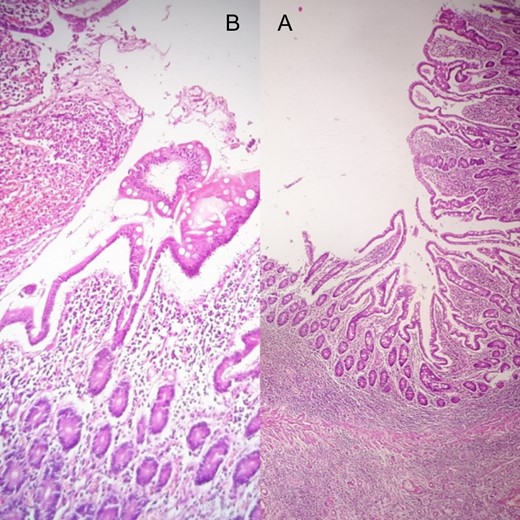

The surgical steps were (Fig. 4): Antrectomy, resection of the fourth duodenum, end to end third duodenojejunostomy, Omega-Braun gastrojejunostomy, feeding jejunostomy and drainage. Histopathology study revealed a perforated benign gastric ulcer (Fig. 5).

Both of (A) biopsy from the fourth duodenal segment and (B) biopsy from the greater curvature of stomach reveal a perforated benign gastric ulcer.